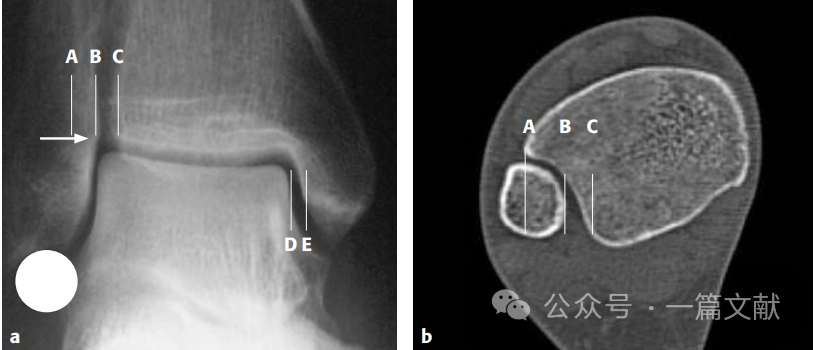

3,透视踝穴位,正常情况下内踝关节间隙DE应小于4mm;胫腓骨外侧间隙BC小于5mm;下图中白色箭头所指的腓骨内侧凸起与胫骨软骨下骨持平,踝穴等宽;图中圆形所示硬币征。

图片图片